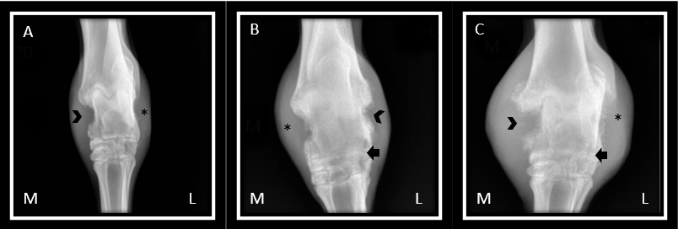

Según lo encontrado al examen clínico y la ecografía se decide realizar un estudio radiológico ortogonal de tarso y de menudillo (desplazamiento de la articulación interfalángica proximal en el examen clínico) del miembro posterior derecho, dicho estudio se realizó varias veces a lo largo de la evolución del caso clínico, siendo que se tomaron vistas radiográficas en el momento inicial del caso, a los 15 días posteriores, a los 4 meses después y un año después (Figura 2). En el examen inicial se realiza una vista lateral del tarso se observa un área de proliferación y reacción perióstica moderada en el aspecto dorsal de la porción distal de la tibia, así mismo en la porción dorsal del tarso central y del tercer hueso tarsiano, la fosa lateral del talus presenta un aspecto radiopaco poco definido, no es posible observar el espacio de la articulación talo-calcanea lateral, evidencia los tubérculos del calcáneo de aspecto poroso, se observa aumento del tamaño del tejido blando en el aspecto dorsal de la articulación (Figura 3).

Radiografía anteroposterior del tarso, se observa marcada reacción perióstica – proliferativa, relacionada a pérdida de la densidad ósea en la porción media y lateral del tarso (punta de flecha), así mismo, anquilosis en la articulación intertarsiana proximal (flecha), se evidencia severo aumento de tamaño del tejido blando periarticular (*). La radiografía A corresponde al momento inicial del caso, radiografía B, fue hecha 15 días después, radiografía C fue realizada 4 meses después.

En el abordaje anteroposterior se encuentra proliferación ósea y reacción perióstica del maléolo medial de la tibia el cual presenta una superficie irregular y disminución de la densidad, lo cual, se hace generalizado para el aspecto medial y lateral del astrágalo, se observa disminución del espacio articular entre las articulaciones intertarsianas proximales e intertarsianas distales, hay lisis óseas en el cuarto hueso tarsiano, finalmente se hace evidente el aumento de tamaño del tejido blando en los aspectos mediales y laterales de la articulación tarsiana . En la radiografía lateral del menudillo se encuentra luxación de la articulación interfalángica proximal, los sesamoideos proximales se observa con un patrón apolillado con múltiples zonas focales de lisis ósea y perdida de densidad. Con la evolución del proceso inflamatorio articular se evidenciaron severos cambios relacionados con lisis ósea, aumento de la reacción proliferativa, y deformación severa de la articulación tarso-tibial, estos procesos fueron observados a los 4 meses y al año posterior al inicio del caso clínico.

Hardy (11), menciona que el estudio radiográfico en pacientes con enfermedad articular es necesario ya que puede correlacionarse con los hallazgos clínicos presentes en el examen físico del paciente, a su vez describe lesiones como disminución de la opacidad a nivel del hueso cortical, reacción perióstica exacerbada, aumento del tamaño y la densidad de la cápsula articular y aumento del líquido sinovial (11), en un estudio realizado por Raes (12), encontró que el 69.7% (62/89) de los animales evaluados tuvieron hallazgos radiográficos relacionados con lesiones compatibles con artritis (12), estos hallazgos radiológicos se relacionan con el estudio realizado ya que la paciente presentó aumento del tamaño articular, área de proliferación y reacción perióstica moderada en el aspecto dorsal de la porción distal de la tibia, porción dorsal del tarso central y del tercer hueso tarsiano; la fosa lateral del talus presenta un aspecto radiopaco poco definido, no es posible observar el espacio de la articulación talo-calcánea lateral, se evidencia los tubérculos del calcáneo de aspecto poroso, se observa aumento del tamaño del tejido blando en el aspecto dorsal de la articulación.